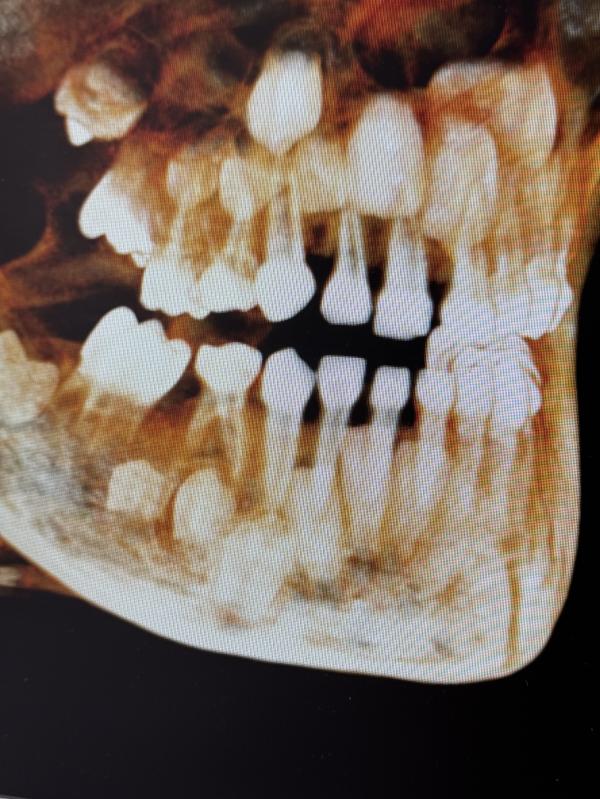

Сын и ортодонт.

У Льва поздние зубы и ранняя смена. В 3 года ему экстренно удалили жевательный молочный зуб. На его месте уже вылез коренной , и он встает не на свое место. История , что молочные будут сменяться сами - не наш случай. Сказали вся смена только через удаление. В июле будем удалять нижние передние , так как коренные уже пошли в рост по диагонали к языку , а корень у молочного даже не планирует рассасываться. В декабре установка пластины на нижнюю челюсть , что бы расширить и удержа...